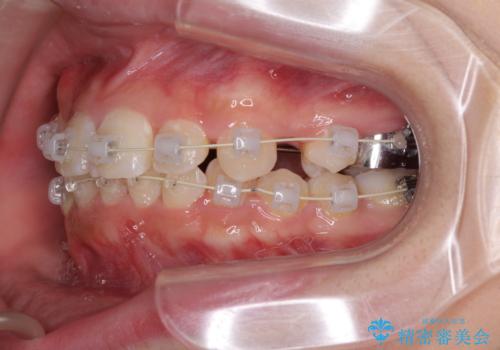

インビザラインが続けられない ワイヤー矯正での抜歯矯正 その2

- 八重歯やデコボコをインビザラインで治療したいとのことで来院された患者様です。

インビザライン単体で治療を行うには叢生が強いと判断されたため、事前にワイヤー装置で抜歯矯正を行い、ある程度改善してからインビザラインにて仕上げていくこととしました。